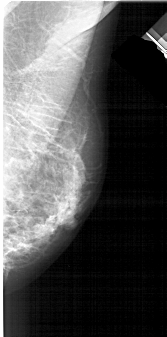

A_1938_1.LEFT_MLO

LEFT_MLO LINES 5101 PIXELS_PER_LINE 2506 BITS_PER_PIXEL 12 RESOLUTION 43.5 OVERLAY